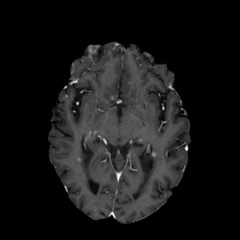

Objectives: This work aims to explore the impact of multicenter data heterogeneity on deep learning brain metastases (BM) autosegmentation performance, and assess the efficacy of an incremental transfer learning technique, namely learning without forgetting (LWF), to improve model generalizability without sharing raw data. Materials and methods: A total of six BM datasets from University Hospital Erlangen (UKER), University Hospital Zurich (USZ), Stanford, UCSF, NYU and BraTS Challenge 2023 on BM segmentation were used for this evaluation. First, the multicenter performance of a convolutional neural network (DeepMedic) for BM autosegmentation was established for exclusive single-center training and for training on pooled data, respectively. Subsequently bilateral collaboration was evaluated, where a UKER pretrained model is shared to another center for further training using transfer learning (TL) either with or without LWF. Results: For single-center training, average F1 scores of BM detection range from 0.625 (NYU) to 0.876 (UKER) on respective single-center test data. Mixed multicenter training notably improves F1 scores at Stanford and NYU, with negligible improvement at other centers. When the UKER pretrained model is applied to USZ, LWF achieves a higher average F1 score (0.839) than naive TL (0.570) and single-center training (0.688) on combined UKER and USZ test data. Naive TL improves sensitivity and contouring accuracy, but compromises precision. Conversely, LWF demonstrates commendable sensitivity, precision and contouring accuracy. When applied to Stanford, similar performance was observed. Conclusion: Data heterogeneity results in varying performance in BM autosegmentation, posing challenges to model generalizability. LWF is a promising approach to peer-to-peer privacy-preserving model training.